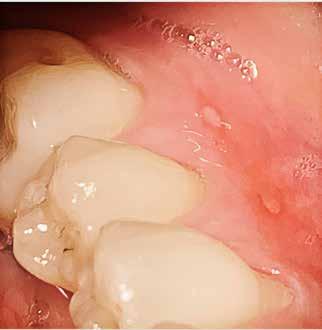

ÅR EN RODBEHANDLET TAND har nået et punkt, hvor tandsubstansen er stærkt reduceret pga. cuspisfraktur, caries, fyldninger eller som følge af endodontisk behandling (Fig. 1A og B), kan det være indiceret, at tanden genopbygges med stift, opbygning samt støbt restaurering (1-5). Førstnævnte for at opnå tilstrækkelig retention af opbygningen. Det er udbredt, at guttaperkafjernelse er mekanisk baseret med anvendelse af et roterende bor (Fig. 1C) (3,6). Boret placeres over rodfyldningen, hvorefter den koronale del samt noget af rodkanalvæggen fjernes mekanisk (4). Den mest apikale del af rodfyldningen bibeholdes, for at denne fortsat er tæt (2,3). En af udfordringerne ved en optimal guttaperkafjernelse samt stiftudboring er muligheden for at følge rodfyldningen uden at afvige fra rodkanalen (7,8). Perforation af tandroden kan ske ved ukorrekt vinkling (Fig. 1C og D), og risikoen forstærkes yderligere ved kraftigt reduceret tandsubstans i den cervikale del af kronen (9,10). Inspektion og belysning kan være besværliggjort, og endelig kan rodfyldningen være meget hård, hvilket komplicerer den taktile sansning under præparationen (9,11). Den utilsigtede vinkling af stiftudboringen, ultimativt rodperforationen,

Ifølge Tandlægeforeningens Tandskadeforsikring udgjorde de årlige tilfælde af rodperforation ved stiftudboring med anvendelse af bor (i forbindelse med genopbygning af tand) gennemsnitligt 55 tilfælde over de sidste fem år (13). Eftersom disse tal kun har at gøre med officielle rapporterede begivenheder, afspejler det sandsynligvis kun ”toppen af isbjerget”, og derfor er komplikationer under stiftudboring forventeligt højere (14). Samlet set er det relevant at undersøge, om der forefindes en mere dentinbesparende samt potentielt komplikationsnedsættende procedure ved guttaperkafjernelse, når forberedelse til rodstiftplacering udføres.